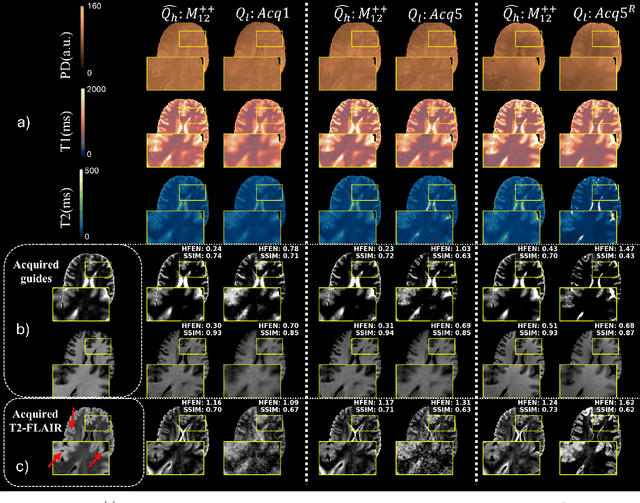

Abstract:High-resolution (HR) quantitative MRI (qMRI) relaxometry provides objective tissue characterization but remains clinically underutilized due to lengthy acquisition times. We propose a physics-informed, self-supervised framework for qMRI super-resolution that uses routinely acquired HR weighted MRI (wMRI) scans as guidance, thus, removing the necessity for HR qMRI ground truth during training. We formulate super-resolution as Bayesian maximum a posteriori inference, minimizing two discrepancies: (1) between HR images synthesized from super-resolved qMRI maps and acquired wMRI guides via forward signal models, and (2) between acquired LR qMRI and downsampled predictions. This physics-informed objective allows the models to learn from clinical wMRI without HR qMRI supervision. To validate the concept, we generate training data by synthesizing wMRI guides from HR qMRI using signal equations, then degrading qMRI resolution via k-space truncation. A deep neural network learns the super-resolution mapping. Ablation experiments demonstrate that T1-weighted images primarily enhance T1 maps, T2-weighted images improve T2 maps, and combined guidance optimally enhances all parameters simultaneously. Validation on independently acquired in-vivo data from a different qMRI sequence confirms cross-qMRI sequence generalizability. Models trained on synthetic data can produce super-resolved maps from a 1-minute acquisition with quality comparable to a 5-minute reference scan, leveraging the scanner-independent nature of relaxometry parameters. By decoupling training from HR qMRI requirement, our framework enables fast qMRI acquisitions enhanced via routine clinical images, offering a practical pathway for integrating quantitative relaxometry into clinical workflows with acceptable additional scan time.